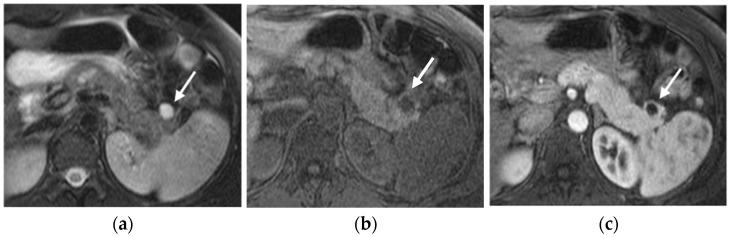

Multiple endocrine neoplasia type 1 (MEN-1) is an autosomal dominant inherited syndrome characterized by a genetic predisposition for the development of specific hormone-secreting tumors. Effective diagnosis and management of MEN-1 require genetic testing, regular surveillance, and imaging follow-up to detect and monitor tumor growth or recurrence and to plan for surgical intervention. The aim of this narrative review is to provide an overview of the current imaging modalities and their role in the diagnosis and follow-up of patients affected by MEN-1, focusing on the detection and characterization of associated neoplasms. The knowledge of the most frequent MEN-1 associated neoplasms and their imaging features is crucial for an accurate diagnosis, management, and treatment.

1型多发性内分泌肿瘤(MEN-1)是一种常染色体显性遗传综合征,其特征是具有发生特定激素分泌肿瘤的遗传易感性。MEN-1的有效诊断和管理需要进行基因检测、定期监测以及影像学随访,以检测和监测肿瘤生长或复发,并为手术干预制定计划。本叙述性综述的目的是概述当前的影像学检查方法及其在MEN-1患者诊断和随访中的作用,重点关注相关肿瘤的检测和特征描述。了解最常见的与MEN-1相关的肿瘤及其影像学特征对于准确的诊断、管理和治疗至关重要。